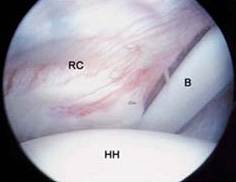

Here are parts of the shoulder joint as seen trhough an arthroscope: the rotator cuff (RC), the head fo the humerus (HH), and the biceps tendon (B).